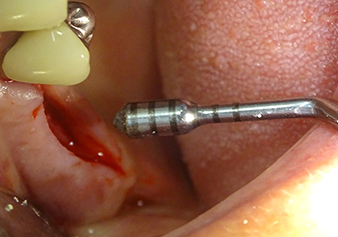

Following atraumatic preparation of the mucoperiosteal flap, the implant position was marked with the I1 instrument and the site prepared – until initial resistance was felt. Piezosurgical instruments were used in an up and down movement without any pressure being exerted. The piezoelectric vibration produced the desired and efficient cavitation.

The I2A instrument (diameter 2.0 mm) was then used to perforate the sinus floor intermittently and on the smallest scale possible. This special piezosurgical method ensures that the Schneiderian membrane is not damaged. When the Z25P was used, the membrane was already lifted slightly by the coolant supplied via the instrument tip (Fig. 3). The coolant quantity was just 50% in order to avoid high pressure in the implant bed.

The Schneiderian membrane is carefully detached with the Z25P instrument (phase 1)

Fig.3: Following marking of the implant position and initial expansion of the bed, the Schneiderian membrane is carefully detached with the Z25P instrument (phase 1).